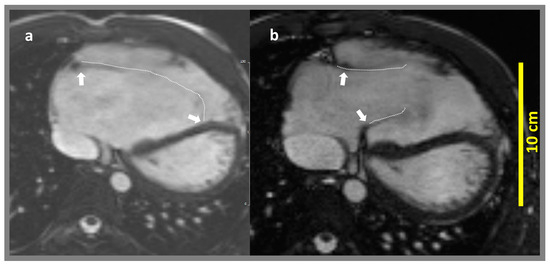

2.2. CMR Acquisition Protocol

2.3. CMR Feature Tracking